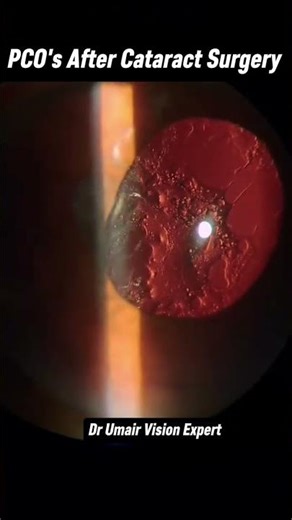

Complications - Cloudy Vision

Lens Options - Clouding